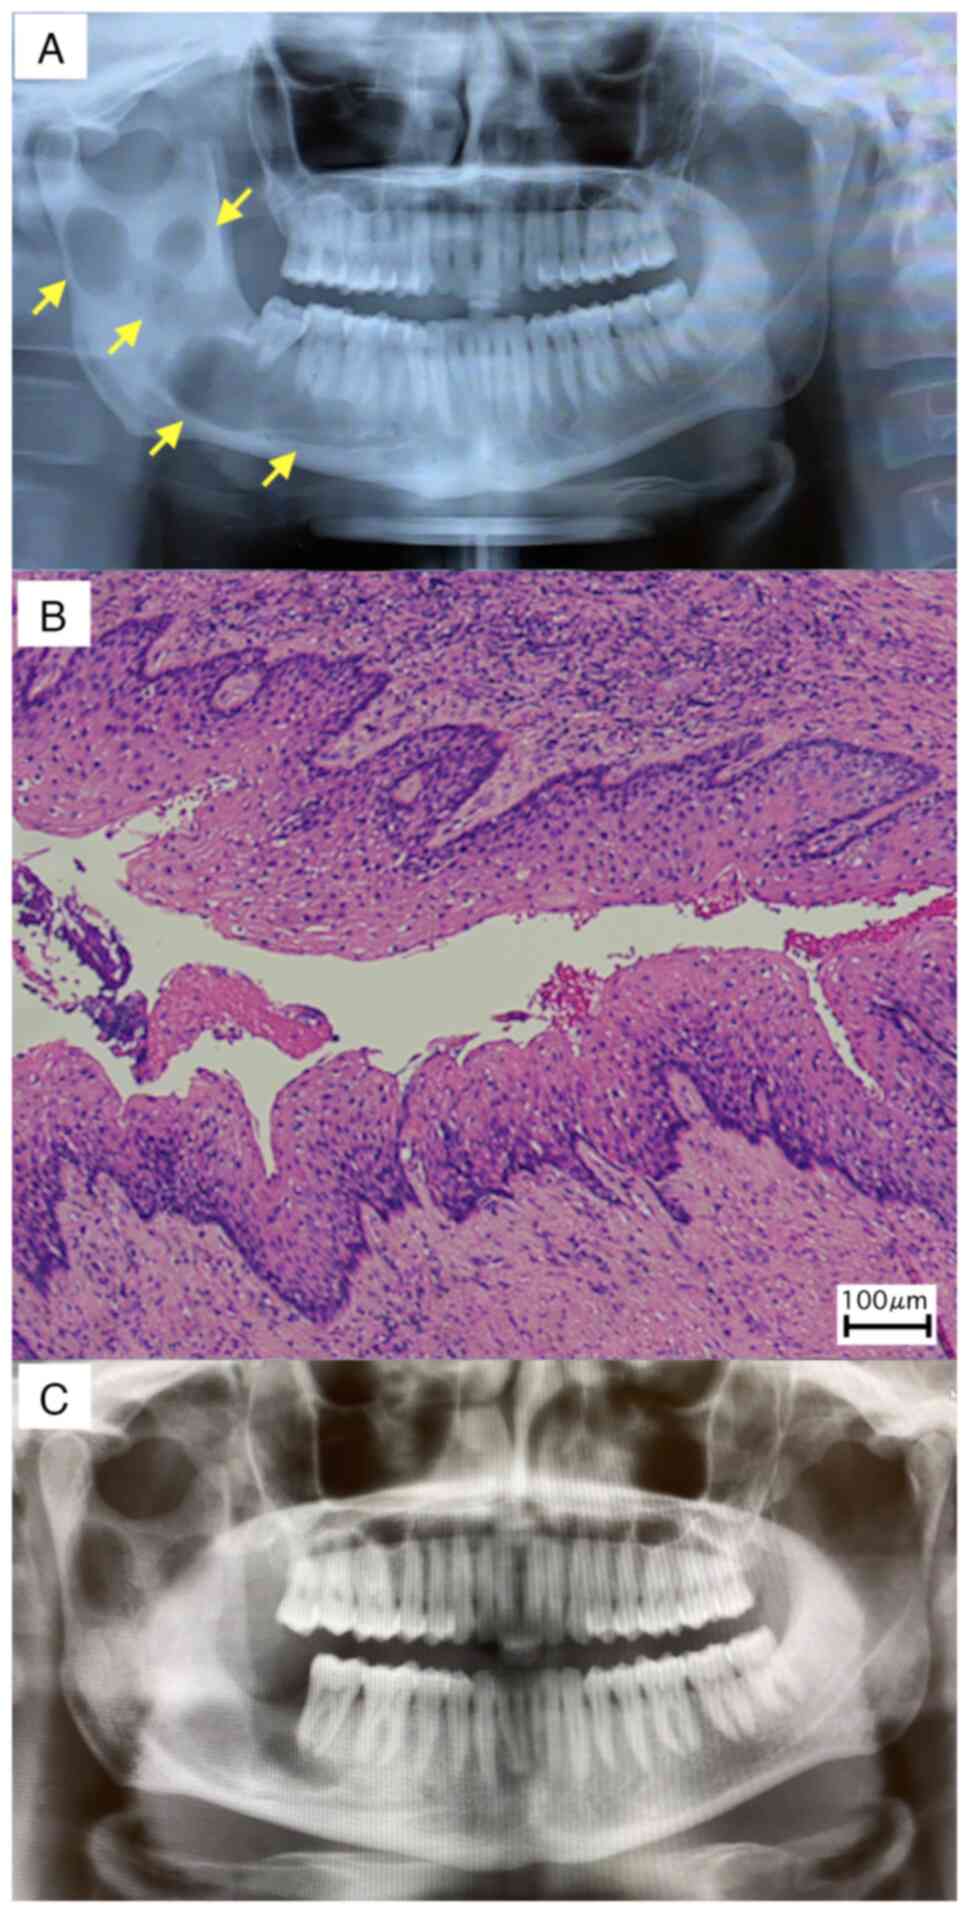

On the first visit to the referral hospital, a

panoramic radiographic examination revealed a multivesicular cyst

formation extending from the right mandibular body to the base of

the condyle (Fig. 1A).

The histopathological result of the cyst excised

during surgery was OKC (Fig. 1B).

Furthermore, the postoperative panoramic radiographic examination

showed that all cysts were removed (Fig. 1C). At the time of their first visit